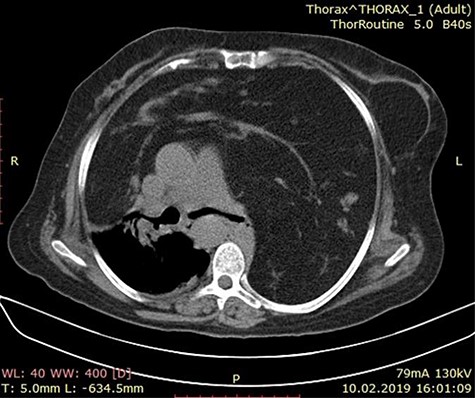

Axial chest CT image showing a mass lesion with wide range of fat density filling both hemithorax was observed, including linear and nodular densities in the right hemithorax. A dense retrosternal mass displacing both lungs and chest. No evidence of invasion is seen.